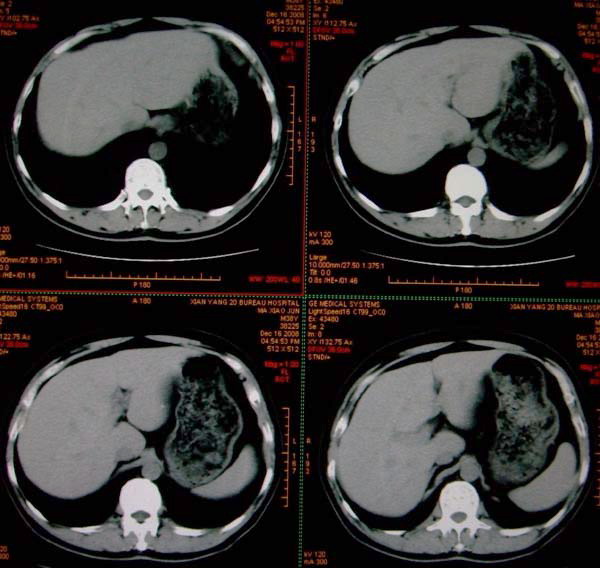

标题: CT17174:M38Y,体检超声提示右肾发育不良,病人无明显不适 [打印本页]

标题: CT17174:M38Y,体检超声提示右肾发育不良,病人无明显不适

右肾发育不良;考虑左肾下极血管平滑肌脂肪瘤可能,建议增强。

右肾微小发育不良  左肾下极错构可能

1)左肾下极占位性病变,不排除肾癌可能;建议行进一步检查。2)右肾发育不良。

左肾下极占位性病变,不排除肾癌可能;建议增强及明确内部组织ct值。右肾发育不良。

右肾发育不良。左肾代偿。左肾下极占位,性质待定,建议强化。

右肾发育不良。左肾下极囊实性占位,建议增强。